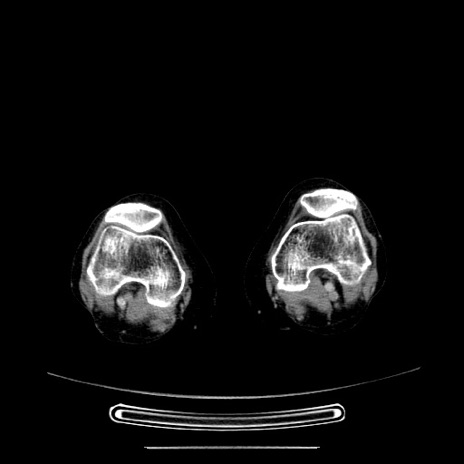

【症例】70歳代女性

【主訴】お腹が張る

【現病歴】1週間くらい前から腹部膨満の自覚あり。昨日夜から増悪したため、本日救急外来受診。

【身体所見】意識清明、BT 36.5℃、BP 165/106mmHg、HR 80bpm、SpO2 98%、腹部:膨満、軟、自発痛・圧痛なし、触診にて不快感あり、腸蠕動音:減弱

【データ】WBC 12600、CRP 1.04